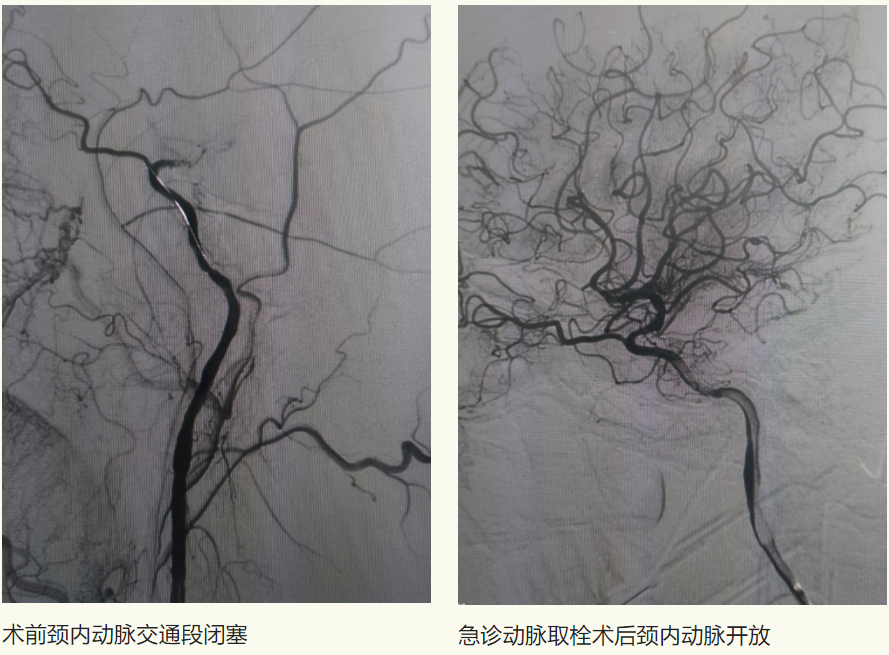

6月10日,家住富区74岁的李先生因“头晕伴行走不稳多年”,来到齐医附属一院就诊。行头CTA检查提示左侧锁骨下动脉管腔重度狭窄、双侧颈内动脉颅内段钙化斑块、管腔轻-中度狭窄、左侧大脑前动脉A1段重度狭窄。患者饱受疾病折磨,长年头晕给生活带来诸多不便,生活质量下降。以往此类患者需前往哈尔滨或者北京等著名医院进行介入手术治疗,大大增加了患者就医困难及经济负担。李先生经多方咨询,了解到刘忠锦副院长为神经介入专家,找到了附属一院刘忠锦副院长来完成治疗。

刘忠锦副院长经过仔细的问诊、查体后和家属详细的进行了沟通,患者选择相信附属一院的技术,决定住院进行手术治疗。入院后刘忠锦副院长带领神经介入团队及神经内五科医生认真地查房及阅片,经全脑血管造影诊断为左侧锁骨下动脉重度狭窄、锁骨下动脉盗血综合征,并制定了手术方案。

6月12日,经过完善的术前准备后,刘忠锦副院长带领神经介入团队为患者行锁骨下动脉支架植入术,术后支架形态良好,前向血流恢复,左侧椎动脉血流较手术前明显改善,且无并发症发生。

术后恢复正向血流